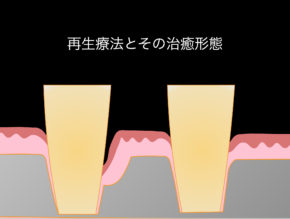

歯周組織再生療法(再生療法)とは?

しかしながら、歯周病治療の中で歯周外科手術と呼ばれる治療方法があり、

その中でも、歯周組織再生療法と呼ばれる失った骨を再生させる方法もございます。

当院では、歯周病治療に真摯に取り組み10年以上の歯周病治療の再生療法の実績がございます。

下記に10年前に行った再生療法の症例をご紹介します。

失った骨の形態や噛み合わせなどにより、全ての患者様に再生療法が適応できる訳ではないですが、現在では症例や材料により保険適応ができる症例もございます。